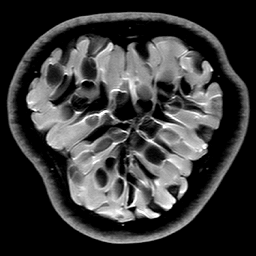

|

|

|

| Original image | Gauss. to DB4, err=31.54% | Gauss. to Flip DB4, err=31.51% |

|

|

|

| Subsampling pattern | DFT to DB4, err=10.96% | DFT to Flipped DB4, err=99.3% |

Since it will become important later, we now describe a quick and simple test, which we call the flip test, to investigate the presence or absence of an RIP. Success of this test suggests the existence of an RIP and failure demonstrates its lack.

Let be a sensing matrix, an image and a sparsifying transformation. Recall that sparsity of the vector is unaffected by permutations. Thus, let us define the flipped vector

and using this, we construct the flipped image Note that, by construction, we have . Now suppose we perform the usual compressed sensing reconstruction (1) on both and , giving approximations and . We now wish to reverse the flipping operation. Thus, we compute which gives a second approximation to the original image .

This test provides a simple way to investigate whether or not the RIP holds. To see why, suppose that satisfies the RIP. Then by construction, we have that

Hence both and should recover equally well. In the top row of Figure 1 we present the result of the flip test for a Gaussian random matrix. As is evident, the reconstructions and are comparable, thus indicating the RIP.

Having considered type II problems, let us now examine the flip test for a type I problem. As discussed, in applications such as MRI, X-ray CT, radio interferometry, etc, the matrix is imposed by the physical sensing device and arises from subsampling the rows of the DFT matrix .111In actual fact, the sensing device takes measurements of the continuous Fourier transform of a function . As discussed in BAACHGSCS ; BAGSAIEP , modelling continuous Fourier measurements as discrete Fourier measurements can lead to inferior reconstructions, and worse, inverse crimes. To avoid this, one must consider an infinite-dimensional compressed sensing approach, as in (2). See AHPRBreaking ; BAGSAIEP for details, as well as PruessmannUnserMRIFast for implementation in MRI. However, for simplicity, we shall continue to work with the finite-dimensional model in the remainder of this paper. Whilst one often has some freedom to choose which rows to sample (corresponding to selecting particular frequencies at which to take measurements), one cannot change the matrix .

It is well known that in order to ensure a good reconstruction, one cannot subsample the DFT uniformly at random (recall that the sparsifying transform is a wavelet basis), but rather one must sample randomly according to an appropriate nonuniform density AHPRBreaking ; Candes_Romberg ; Lustig ; WangAcre . See the bottom left panel of Figure 1 for an example of a typical density. As can be seen in the next panel, by doing so one achieves a great recovery. However, the result of the flip test in the bottom right panel clearly demonstrates that the matrix does not satisfy an RIP. In particular, the ordering of the wavelet coefficients plays a crucial role in the reconstruction quality. To explain this, and in particular, the high-quality reconstruction seen in the unflipped case, one evidently requires a new analytical framework.

Note that the flip test in Figure 1 also highlights another important phenomenon: namely, the effectiveness of the subsampling strategy depends on the sparsity structure of the image. In particular, two images with the same total sparsity (the original and the flipped ) result in wildly different errors when the same sampling pattern is used. Thus we conclude that there is no one optimal sampling strategy for all sparse vectors of wavelet coefficients.